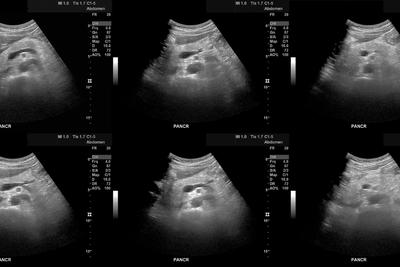

Ecografía abdominal:

Mostró esplenomegalia de 18 cm y riñones agrandados (14 cm) con ecoestructura normal.